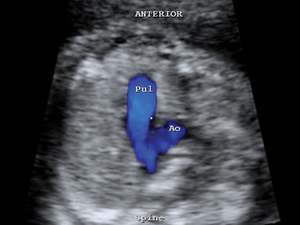

Colour flow of both pulmonary artery and aorta Limps